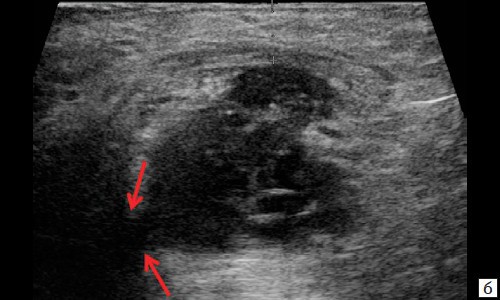

При контрольном исследовании через 3 дня после оперативного вмешательства: описываемое гипоэхогенное жидкостное образование с четкими неровными контурами с наличием неоднородного гиперэхогенного подвижного содержимого уменьшилось в размере до 2,4×1,7×1,8 см и объеме до 3,84 мл (рис. 2, а, б). В подкожно-жировой клетчатке по периферии гипоэхогенного образования отмечается уменьшение степени выраженности сосудистой реакции (рис. 2, в). Описываемый свищевой ход уменьшился в размере до 1,1×0,2×0,5 см (рис. 2, г).

Рис. 2. а, б – В-режим. Через 3 дня после оперативного вмешательства. Описываемое гипоэхогенное жидкостное образование с четкими неровными контурами с наличием неоднородного гиперэхогенного подвижного содержимого уменьшилось в размере до 2,4×1,7×1,8 см, до объема 3,84 мл (стрелки);

г – В-режим. Через 3 дня после оперативного вмешательства. Описываемый свищевой ход уменьшился в размере до 1,1×0,2×0,5 см (стрелки).